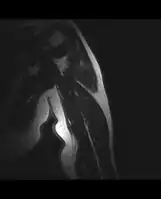

MRI mid-upper arm -

MRI mid-arm axial view -